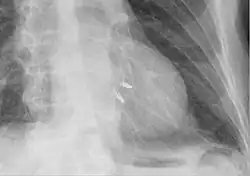

Chest radiograph showing two MitraClips projecting over the heart. | |